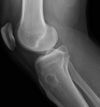

- Restoring anatomical alignment of fracture or dislocation (see image for why)